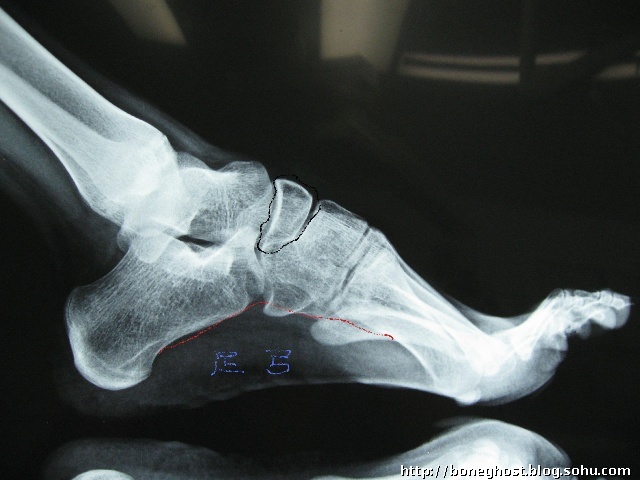

黑线画出的就是足舟骨,姚明骨折的那块骨头.